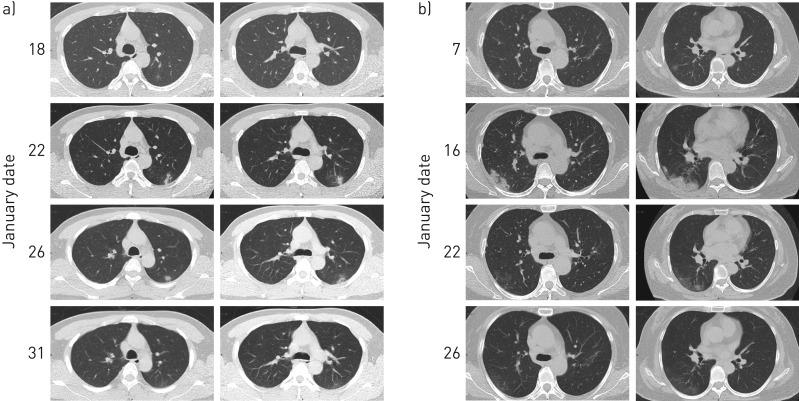

The novel coronavirus, severe acute respiratory syndrome coronavirus 2 (SARS-CoV-2), infected over 3300 healthcare workers in early 2020 in China. Little information is known about nosocomial infections of healthcare workers in the initial period. We analysed data from healthcare workers with nosocomial infections in Wuhan Union Hospital (Wuhan, China) and their family members.

We collected and analysed data on exposure history, illness timelines and epidemiological characteristics from 25 healthcare workers with laboratory-confirmed coronavirus disease 2019 (COVID-19) and two healthcare workers in whom COVID-19 was highly suspected, as well as 10 of their family members with COVID-19, between 5 January and 12 February 2020. The demographics and clinical features of the 35 laboratory-confirmed cases were investigated and viral RNA of 12 cases was sequenced and analysed.

Nine clusters were found among the patients. All patients showed mild to moderate clinical manifestation and recovered without deterioration. The mean period of incubation was 4.5 days, the mean±sd clinical onset serial interval (COSI) was 5.2±3.2 days, and the median virus shedding time was 18.5 days. Complete genomic sequences of 12 different coronavirus strains demonstrated that the viral structure, with small irrelevant mutations, was stable in the transmission chains and showed remarkable traits of infectious traceability.